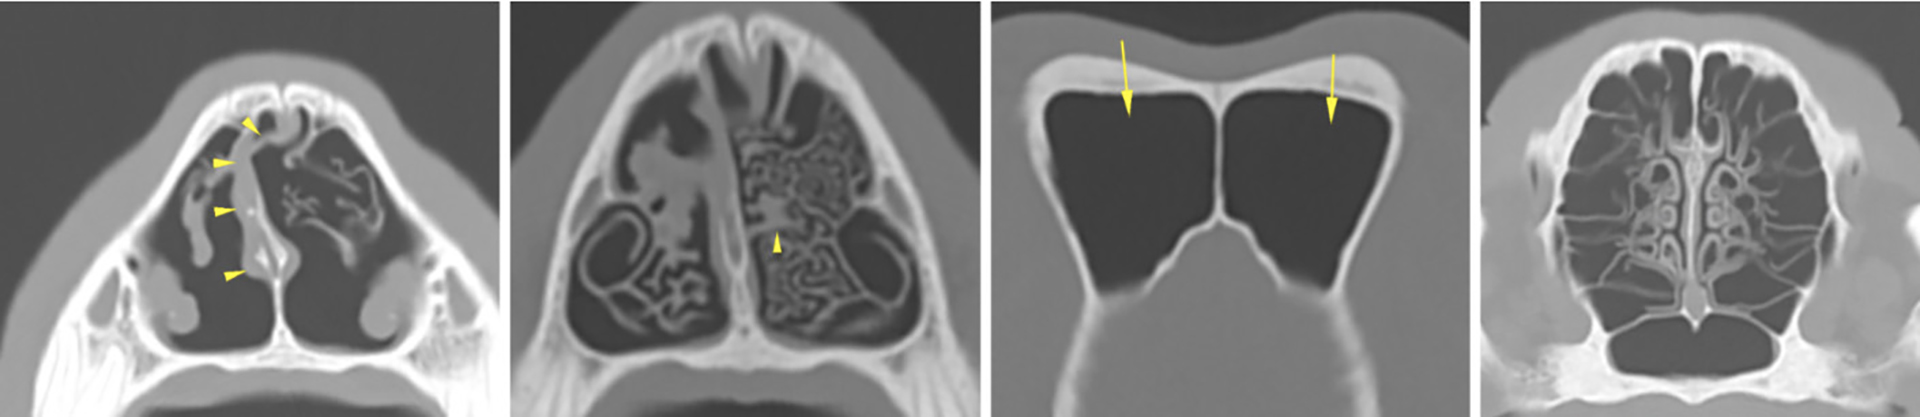

Figur 8. Rhinoskopiundersøkelse uten tegn til nekroser eller plakkformasjoner etter vellykket behandling av aspergillose.

Foto: Caroline Solberg Graham

Det ble anvendt samme anestesiprotokoll og medisineringsplan som sist, med unntak av paracetamol og fentanyl CRI. Ved rhinoskopiundersøkelsen var det ikke lenger synlige tegn til aspergillose. Slimhinnene var for det meste rosa av farge (Figur 8). I områdene som hadde vært mest affisert av aspergillose ved forrige undersøkelse var slimhinnen mer lyserosa eller hvit, og med rikelige mengder blodforsyning som indikerte sårheling. Det manglet som forventet brusk der nekrotisk vev og brusk var blitt fjernet ved forrige behandling. Det var i tillegg funn av en septumperforasjon. Nesehulen ble spylt med sterilt saltvann under rhinoskopiundersøkelsen. Deponering av klotrimazol i nesen ble gjentatt på samme måte som sist med okkludering av nesen, med unntak av trepanering som ikke ble vurdert som nødvendig (Figur 9). Dette for å bli kvitt potensielle rester av aspergillose i nesehulen som ikke lot seg visualisere via rhinoskopi. Hunden viste ingen nysing i etterkant av behandlingen.